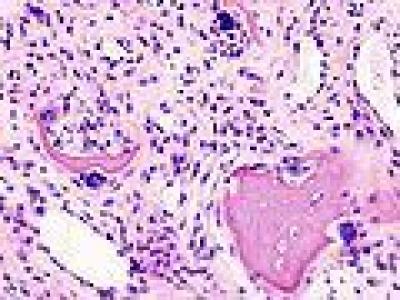

JAMA Dermatology reports a retrospective cohort study from Johns Hopkins reviewing mimic of dermatomyositis (DM), suggesting that DM and especially clinically amyopathic DM (CADM) are commonly and initially misdiagnosed as inflammatory skin disease (ISD).

The study was undertaken to evaluate misdiagnosis patterns and the clinical implications of those with DM and CADM.

Study included adults with confirmed DM or CADM, seen between 2005 and 2023. Duration of misdiagnosis was defined as time between first ISD diagnosis and DM or CADM confirmation.